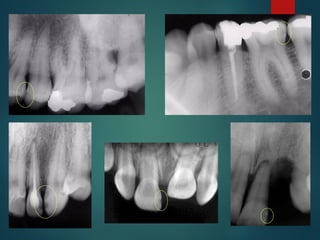

Clasificación Radiográfica

De Las Caries

Incipiente de esmalte

De esmalte

Dentinaria superficial

Dentinaria profunda

Sobreproyectada en cámara pulpar

Penetrante

 Incipiente de esmalte

 De esmalte

 Dentinaria superficial

 Dentinaria profunda

 Sobreproyectada en cámara

pulpar

 Penetrante